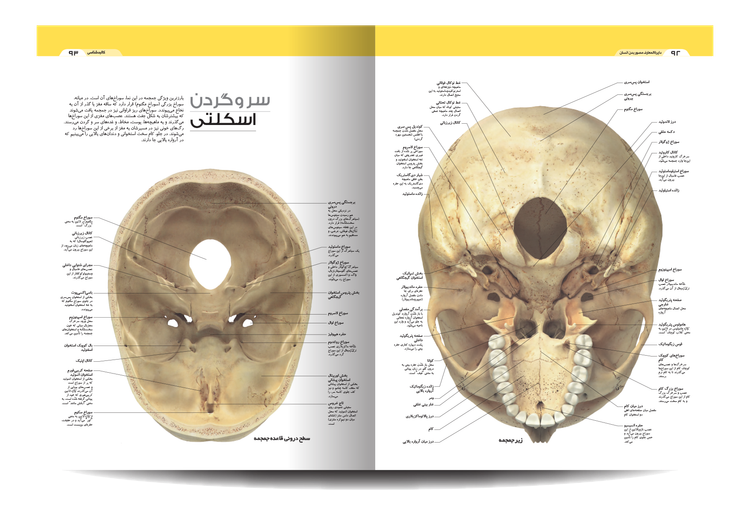

برای درک بدن انسان مدرن ما، این کتاب ابتدا به اجداد ما و چگونگی شکل گیری آناتومی ما توسط تکامل هومو ساپینس میپردازد. به واسطه این کتاب بیاموزید که چگونه می توانیم تکامل را در DNA خود و عملکردهای DNA مشاهده کنیم. در مورد چیزهایی که فقط با میکروسکوپ و سایر ماشینهای تصویربرداری خاص میتوانید ببینید، بخوانید، مانند ساختار سلولی، مسیرهای حرکتی در مغز و عنبیه داخلی. همه این بخشها با هم کار میکنند تا بدن انسان را بسازند. فیزیولوژی بدن ما با جزئیات روشن نوشته شده است. درباره اندامها و سیستمهایی که در داخل کار میکنند، مانند سیستمهای قلبی عروقی، گوارشی و عصبی، بیاموزید.

آناتومی زیبای ما را ببینید و نحوه عملکرد اسکلت، ماهیچه ها و رباط ها را بخوانید. این ویرایش دوم شامل جزئیات بیشتری در مورد مفاصل دست و پا است. کتاب «دایره المعارف مصور بدن انسان» شما را از دوران نوزادی تا پیری می برد و نشان می دهد که بدن ما چگونه رشد می کند و تغییر می کند و چه چیزی ممکن است اشتباه باشد.

این راهنمای تصویری از تصاویر و نمودارهای قابل توجهی برای نگاه کردن به بدن پیچیده و شگفتانگیز ما استفاده میکند. این در قالبی ساده و با توضیحات ساده نوشته شده است تا بهترین نمای کلی از بسیاری از چیزهایی را که ما را انسان میسازند به شما ارائه دهد.